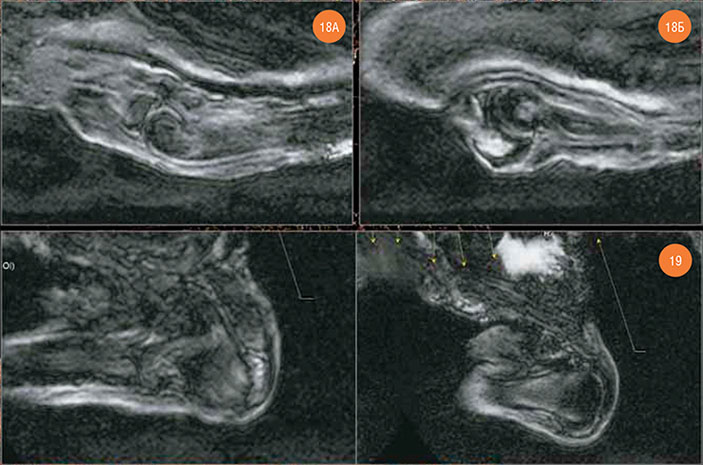

Рис. 18. Левый локтевой сустав. А — articulatio humeroradialis, Б — articulatio humeroulnaris (в структуре olecranon’а — отечный очаг) Рис. 19. Левый плечевой сустав (параллельные срезы)

Поскольку из-за утраты мягких тканей правого плеча уровень МР-сигнала от правого плечевого сустава был низким, для его визуализации была использована технология наложения изображений программы Radiant Dicom Viever 1.9.2. По верхнему контуру головки правой плечевой кости был обнаружен дефект глубиной до 3,5–4,5 мм. Отчетливая отечная структура толщиной до 4 мм в зоне этого дефекта кости явно указывает на прижизненный травматический характер этого изменения. Отечный очаг был обнаружен и в акромеальном конце правой ключицы.

Рис. 20. Правый плечевой сустав. А — нативная томограмма; в акромеальном конце ключицы — очаг отечного плана. Б — технология наложения изображений из программы Radiant Dicom Viever 1.9.2 (64-bit); дефект по верхнему контуру головки плечевой кости